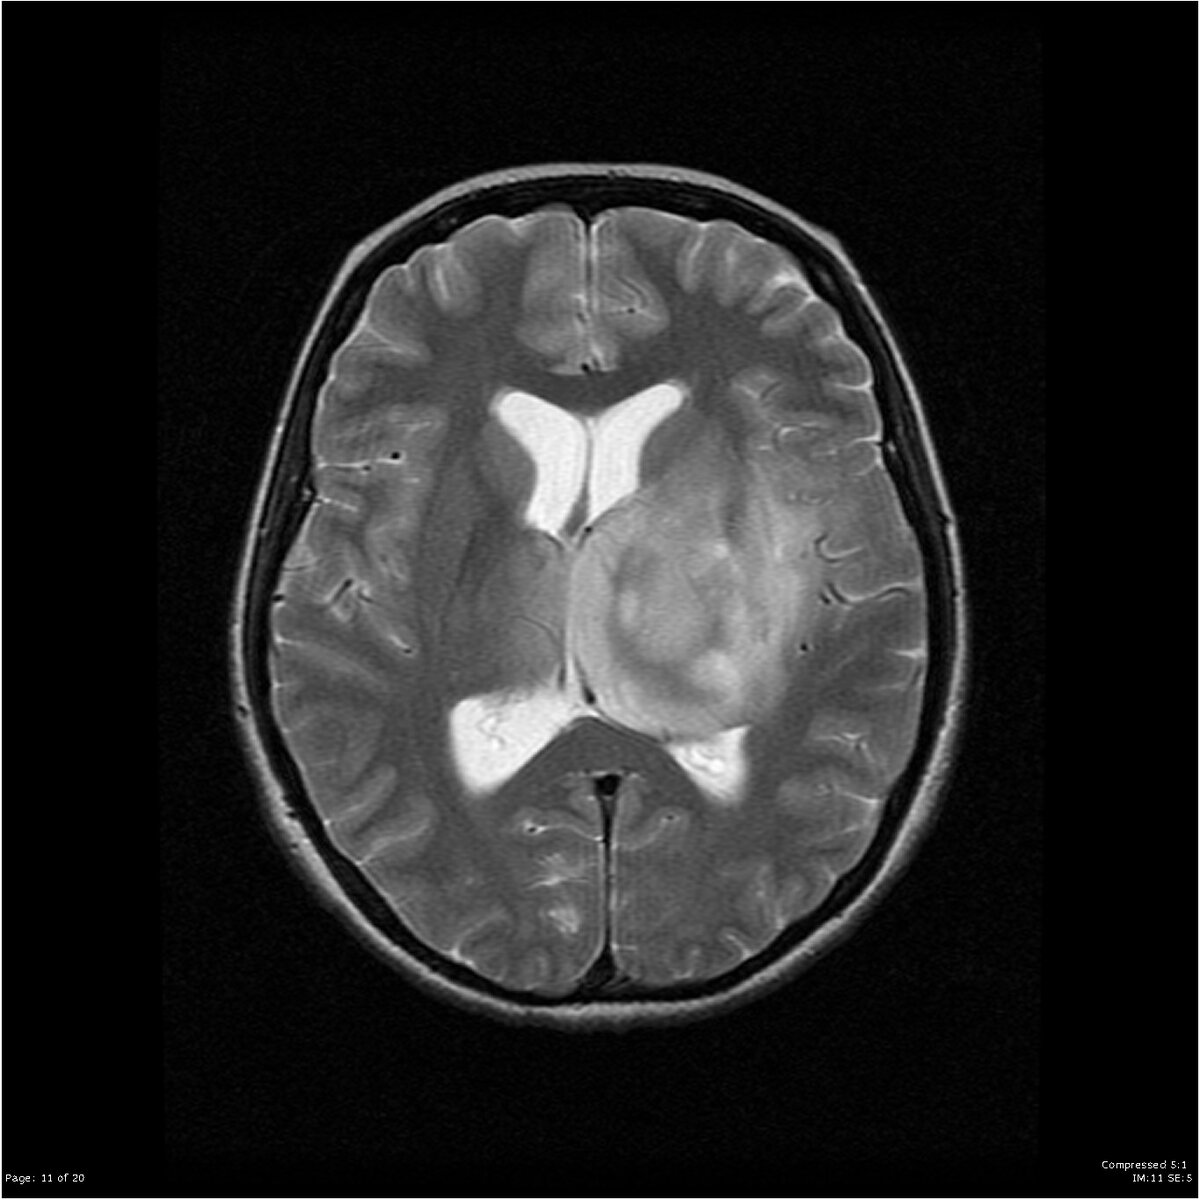

Вот так выглядит результат МРТ. Radiopedia.org